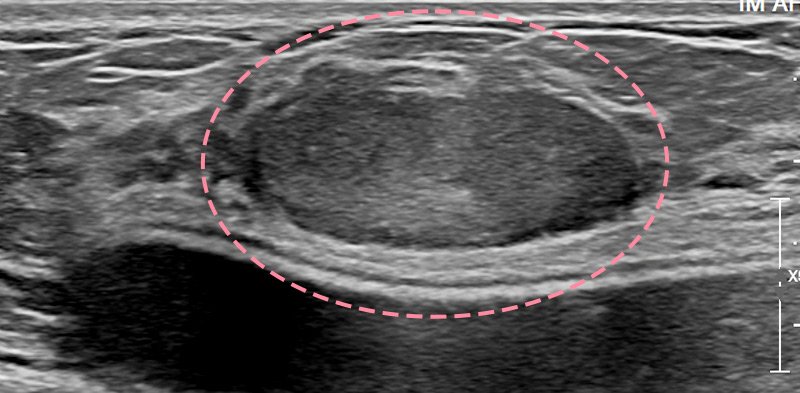

유방 양성 종양은 한 개만 나타나는 것이 아니라 동시다발적으로 생겨나기도 합니다.

여러 개의 양성 종양 제거는 정상적인 유방 조직을 온전히 보전할 수 있도록 섬세한 시술이 필요합니다.

한송이 원장은 다발성 종양 제거에 대한 풍부한 경험을 토대로, 무리 없이 맘모톰 조직검사 및 제거를 진행했습니다.

맘모톰시술 6개월 후 유방초음파 검사 시행 결과 종양이 깨끗하게 제거됨을 확인했으며, 약간의 반흔 조직이 남았으나 시간이 지나면서 대부분 사라지기 때문에 좋은 예후가 기대되었습니다.